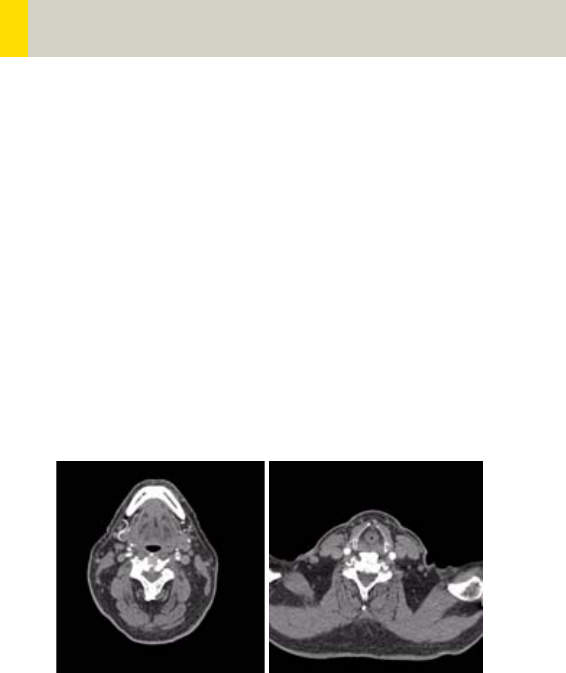

92

Neck 204

•Overview 204

- General Hints 206

- Body Kernels 207

•Scan Protocols 208

- NeckRoutine 208